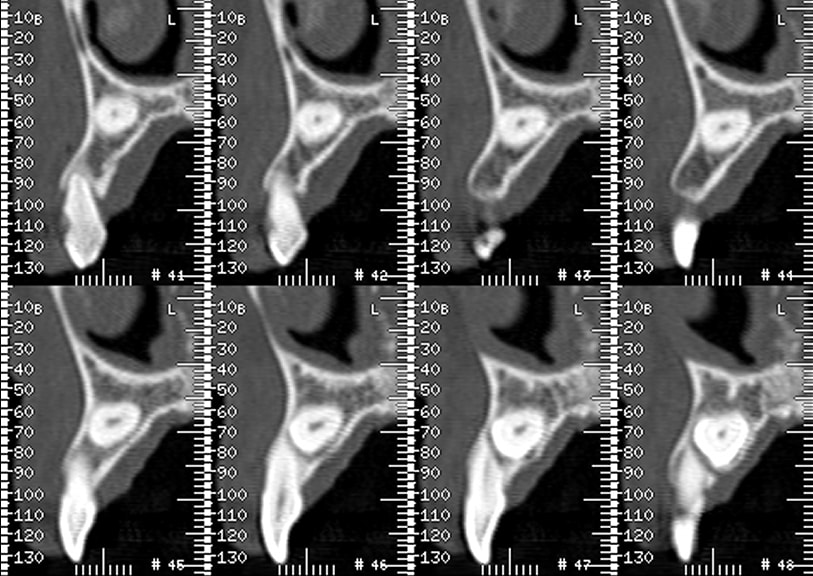

je dois poser un implant en lieu et place de la 13

mais cette 13 est incluse

la patiente a 74 ans

j'ai 6mm

1er cas reussi, tranfixation de la racine: forage facile

2eme cas :transfixation dans la couronne!!! Qforage difficile: ça a du echauffé d’ou l’echec je pense

Pourquoi j’ai tenté: parce que sinon, il fallait avulser la canine incluse ce qui aurait ( et du coup a) fait un gros defaut osseux en vestibulaire; du coup j’ai du faire une allogreffe!!! Gratuite pour le patient bien sur! J’ai joué, j’ai perdu, j’assume!